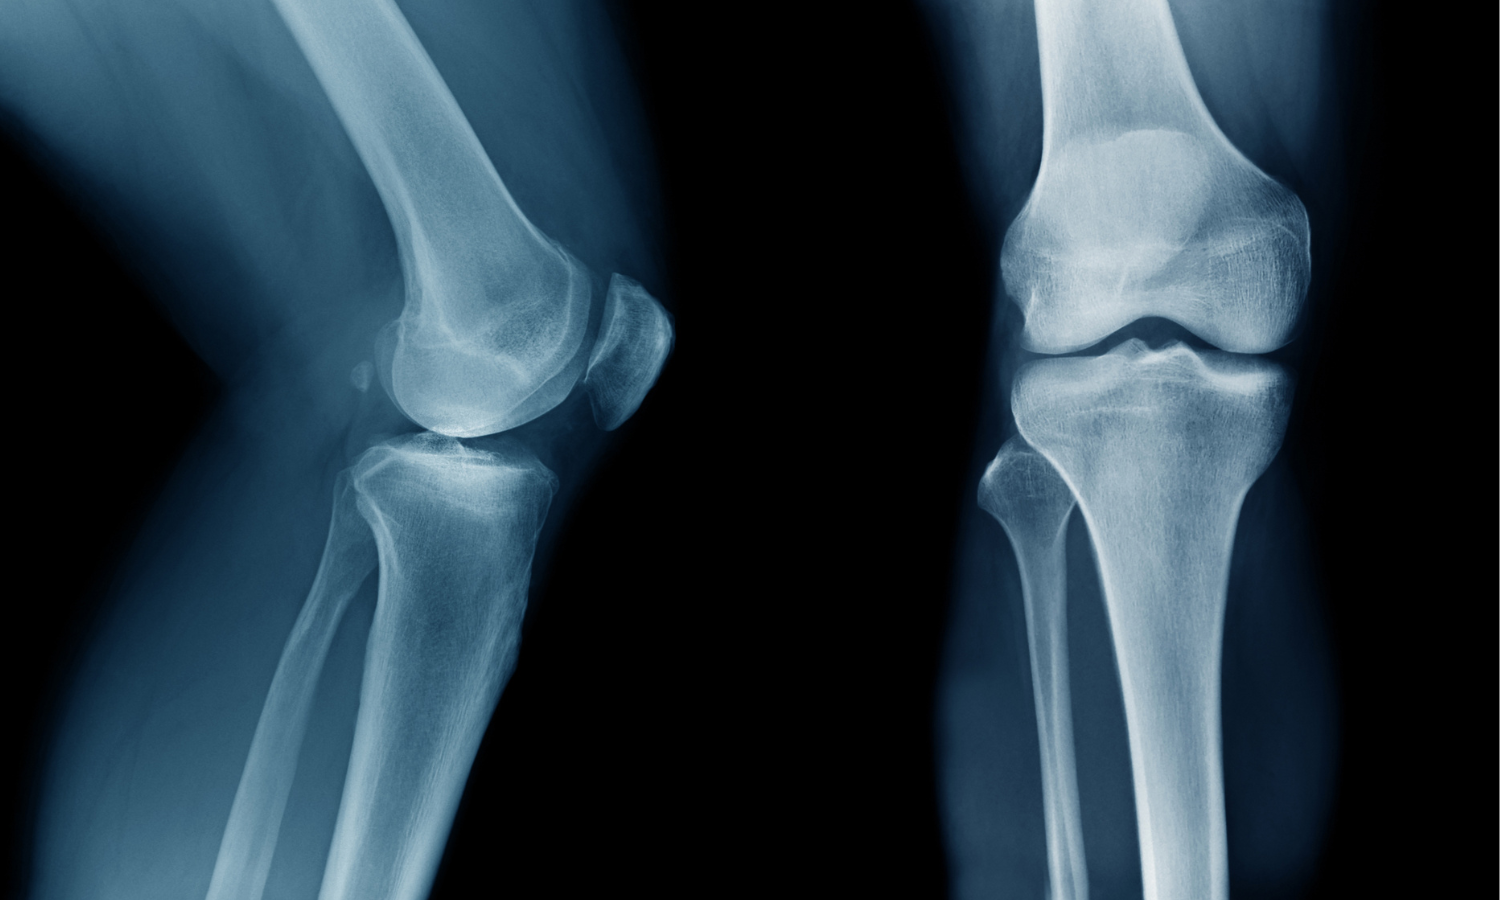

Gli esami come la risonanza magnetica sono strumenti fondamentali perché permettono di osservare le strutture del ginocchio: menischi, legamenti, cartilagine e osso.

Ma c’è un aspetto che questi esami non riescono a raccontare: come il ginocchio funziona durante il movimento.